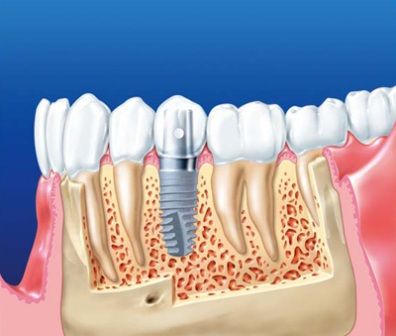

İMPLANT NEDİR? İmplantlar, diş kökü şeklinde titanyumdan hazırlanmış, çene kemiğine küçük bir operasyon ile yerleştirilen suni diş kökleridir. Titanyum doku dostu bir malzemedir. Kemik ile özel bir bağ oluşturarak yerleştirildiği yere, hücresel olarak tutunur. Bu tutunma tamamlandığında (2-6 ay) üst yapı dediğimiz protezi hazırlama işlemine geçilir. Günümüzde implantlar tartışmasız olarak doğal dişe en iyi alternatiftir.

İmplantların Fonksiyonu Nedir? İmplant çene kemiğinize kaynadığından dolayı, yapay dişler için sabit destek sağlarlar. İmplantlara takılan protez ve köprüler, ağzınızın içinde kaymazlar – bu, yemek yemek ve konuşmak için gereklidir. Bu sabit destek , protez ve köprülerin yanı sıra implantlar üzerine yerleştirilen kuronların, geleneksel köprü veya protezlere göre daha doğal hissedilmesini de sağlar.

Endosteal implantlar - bu implantlar, cerrahi yöntemle, çene kemiğine direkt olarak implante edilirler. Çevredeki dişeti dokusu iyileştikten sonra, orijinal implanta bağlantı sağlayacak materyali takmak için ikinci bir operasyon gerekir. Son olarak, yapay diş (veya dişler) tek başına veya köprü ya da protez üzerinde grup halinde implanta takılır.